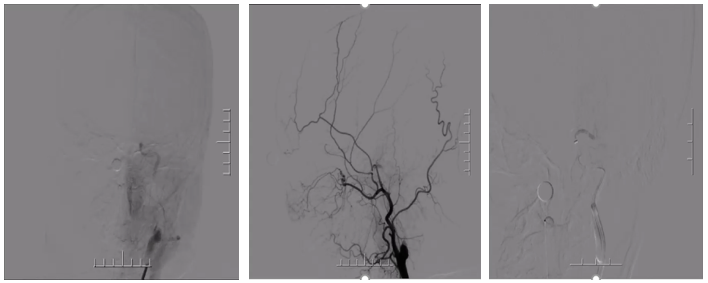

DSA

病历夹什么径技·第151期|串联营病历夹:京广连营_https://www.jmylbn.com_新闻资讯_第8张

病历夹什么径技·第151期|串联营病历夹:京广连营_https://www.jmylbn.com_新闻资讯_第9张

结论:左侧颈动脉起始部位出现断流,右侧颈动脉没有明显代偿,血管形态较光滑。